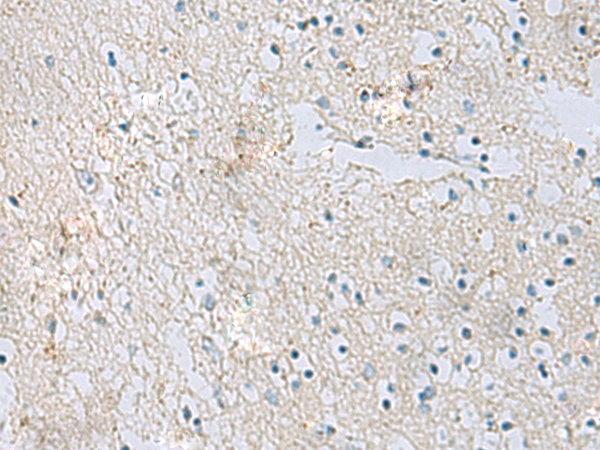

IHC positive control: |

Human brain |

IHC Recommend dilution: |

50-100 |